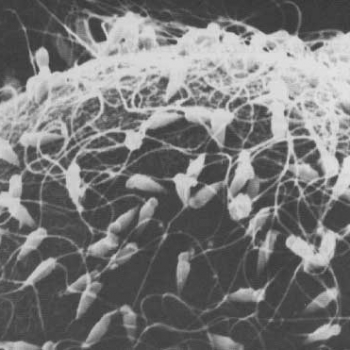

De cada 100 jóvenes con cáncer, ¿en cuántos se trata de un cáncer en el testículo?

1-Cinco 2- Diez 3- Veinte 4- Cuarenta